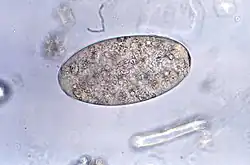

| Eggs of Fasciolopsis buski | |

Microscopic identification of eggs, or more rarely of the adult flukes, in the stool or vomitus is the basis of specific diagnosis. The eggs are indistinguishable from those of the very closely related Fasciola hepatica liver fluke, but that is largely inconsequential since treatment is essentially identical for both.